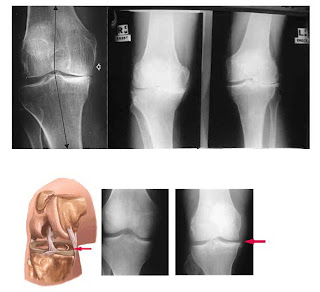

1. Rontgen Tulang

Diagnosis OA lutut biasanya didasarkan pada gambaran klinis dan radiologis. Pada sebagian besar kasus, radiografi pada sendi yang terkena osteoarthritis sudah cukup memberikan gambaran diagnostik. Jarang sekali dibutuhkan peralatan diagnostik yang lebih canggih. Gambaran radiografik yang menyokong diagnostik OA adalah penyempitan celah sendi yang sering kali asimetris (lebih berat pada bagian yang menanggung beban), peningkatan densitas (sklerosis) tulang subkondral, kista tulang, osteofit pada pinggir sendi dan perubahan struktur anatomi sendi (Kalim, 1996). Selain pendapat di atas, kriteria Altman juga merupakan salah satu pedoman diagnosis OA lutut. Bila seseorang ditemukan hanya nyeri lutut, diagnosa OA harus ditambah 3 dari 5 kriteria, yaitu 1) umur di atas 50 tahun, 2) kaku sendi pagi hari kurang dari 30 menit, 3) nyeri tekan pada tulang, 4) pembesaran tulang, 5) perabaan sendi tidak panas. Bila ada gambaran osteofit pada pemeriksaan radiologi, dibutuhkan 1 dari 3 kriteria tambahan, yaitu 1) umur di atas 50 tahun, 2) kaku sendi kurang dari 30 menit, 3) krepitasi (Parjoto, 2000). Dengan rontgen kita dapat mengetahui dengan jelas kerusakan atau perubahan-perubahan yang terjadi pada tulang rawan atau tulang yang diindikasikan mengalami osteoartritis.

Gb. 4. Gambaran rontgen Knee OA